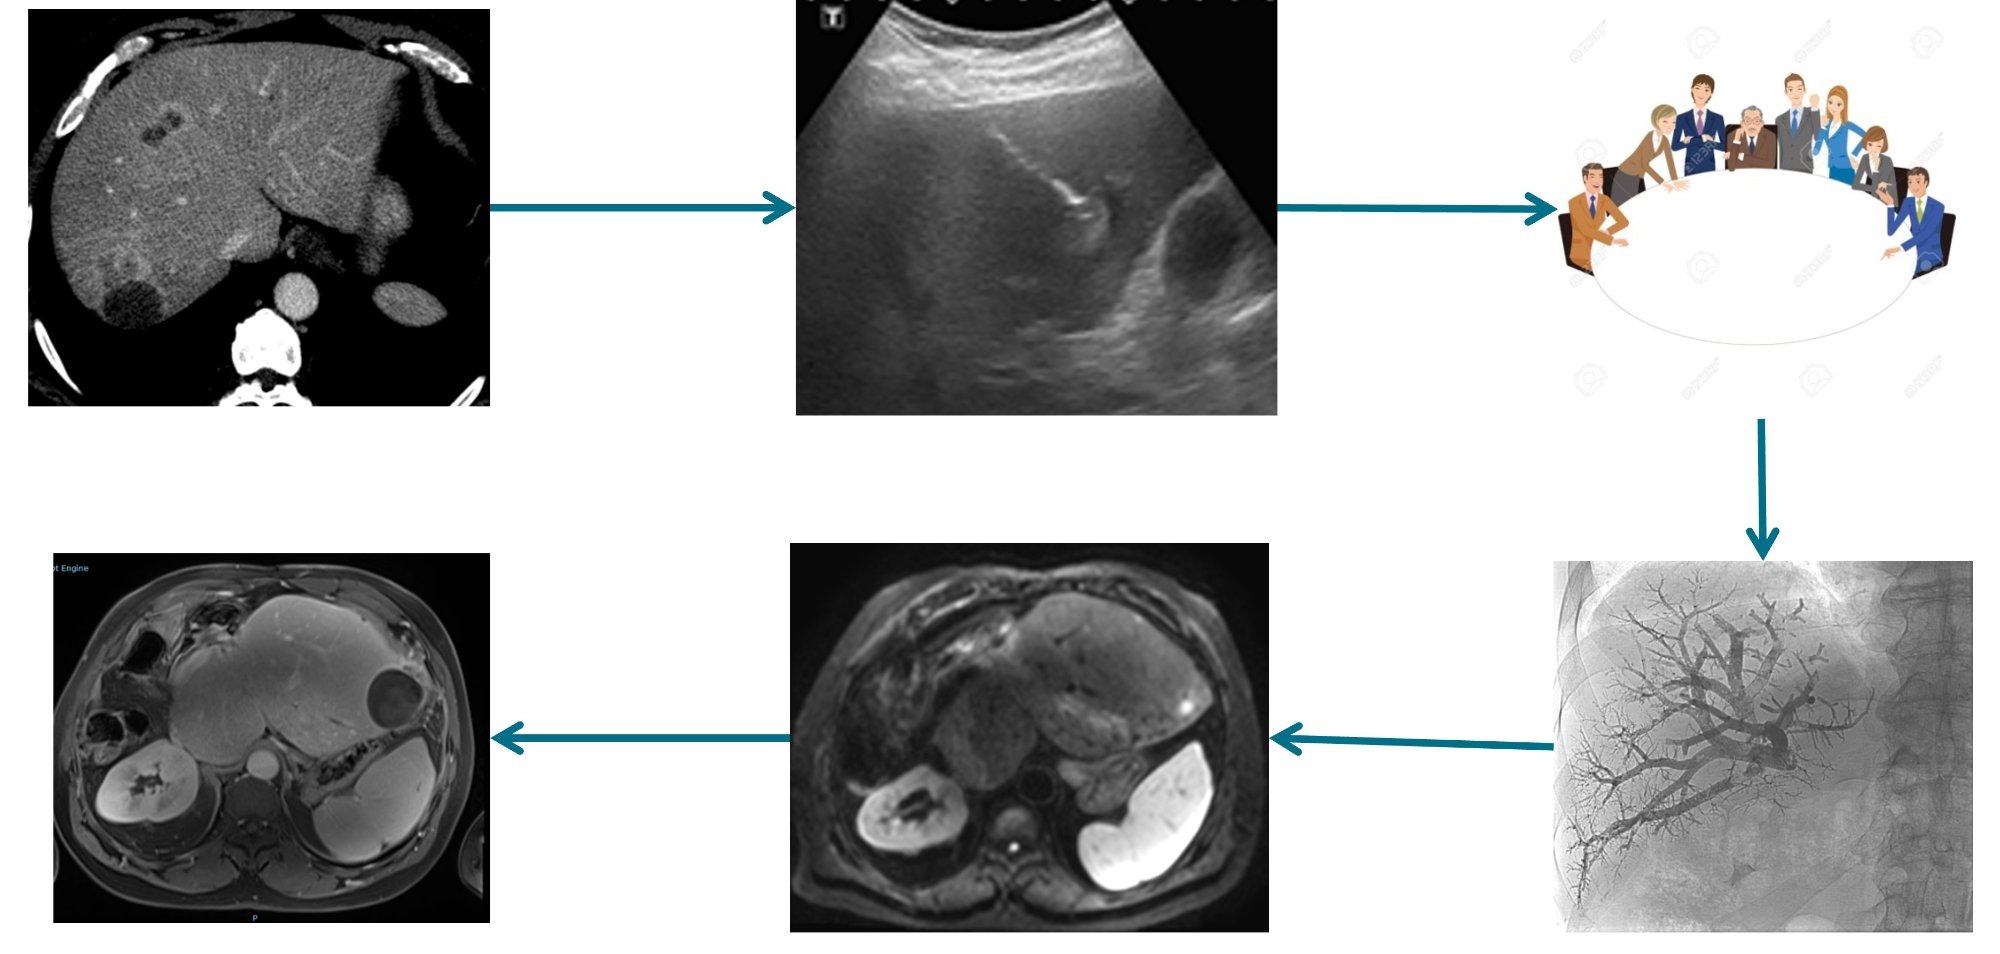

Centre Expert Cancers du Foie

RF, micro-ondes, IRE (lésions péri-biliaires/pancréatiques), TACE, Y90, chirurgie hépatique, transplantation.

Tumeurs du foie

Micro-ondes, RF, cryoablation. IRE (NanoKnife) pour les lésions péri-biliaires.

💉Chimio-embolisation (TACE)

CHC et métastases hépatiques : traitement de référence, zéro dépassement.

☢️Radio-embolisation TheraSphere® (Y90)

Radiothérapie interne sélective par microsphères d'yttrium-90.